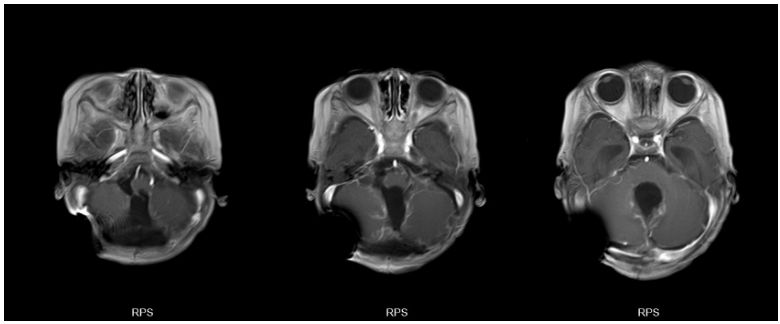

术后1周复查增强MR:

图4. 肿瘤切除术后,术区未见明显强化肿瘤残余,脑积水缓解。同时,由于使用蛇牌可吸收钉固定颅骨,成像无伪影,不影响术后检查。